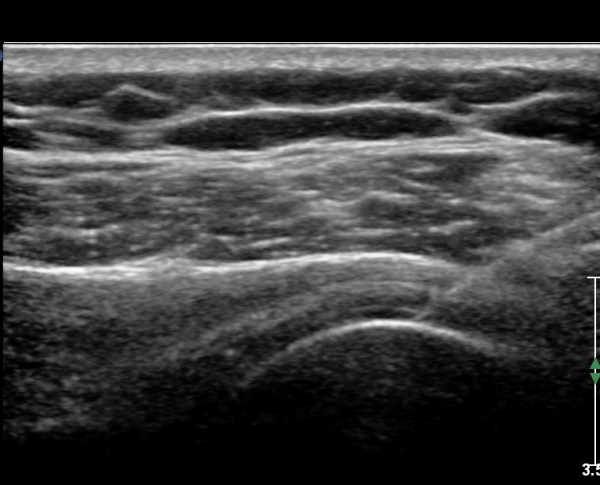

Å½ÃËÀÚ¸¦ ¾à°£ ¿ÜÃøÀ¸·Î À̵¿ÇÏ¿© Á¶ÀýÇÏ´Ï À̵ιڰÇÀÌ °üÂûµÇ°í(»çÁø 6) ¾à°£ ¸»´ÜÀ¸·Î

À̵¿ÇÏ´Ï °ÇÁÖÀ§ ¼ö¾×Àú·ù°¡ °üÂûµÈ´Ù(»çÁø 7).